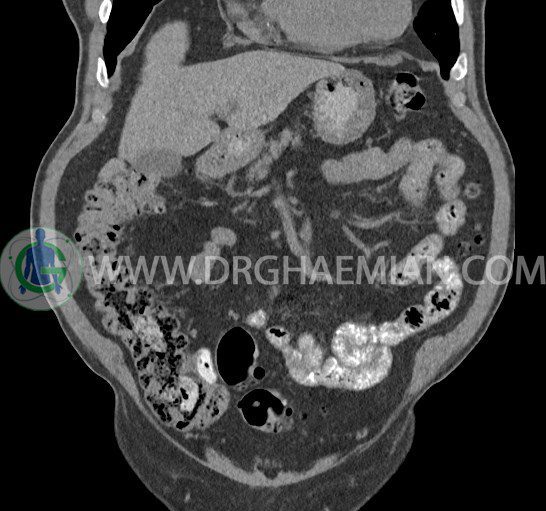

سی تی اسکن لگن یکی از روش های تصویربرداری با سی تی اسکن است. این روش با استفاده از تشعشعات تصاویر عرضی از ناحیه شکمی ایجاد میکند. در این کیس ديورتيكولوزيس، کیست های کورتیکال در هر دو کلیه، لنفادنوپاتی، کلسیفیکاسیون دیواره آئورت و شریان ایلیاک، تغییرات DJD ناحیه توراکولومبار و پروستات بزرگتر از عادی دیده می شود.

در سي تي اسکن اسپيرال شکم و لگن با و بدون کنتراست خوراکی و وريدی (مولتي ديدکتور 16 با مقاطع ظريف و بازسازي هاي ساژيتال و کرونال):

– کيست هاي کورتيکال ساده به قطر 5 mm تا 50 mm در کليه راست و به قطر 5mm تا 55 mm در کليه چپ

– توده ايزودنس به ابعاد mm 17 x 28 در پره ائورت مجاور قسمت تحتاني D3 دئودنوم مطرح کننده لنفادنوپاتي و با احتمال کمتر آنوريسم ترومبوزه (نيازمند مطابقت سونولوژيک)

– کلسيفيکاسيون ديواره آئورت و شريان ها ايلياک همراه با نشانه هاي ترومبوز مورال در بيفورکاسيون ائورت با امتداد به پروگزيمال هاي شريان هاي ايلياک

– ديورتيكولوزيس در کولون نزولي وسيگموئيد

– تغييرات DJD در ناحيه توراکولومبار و

مشهود است.